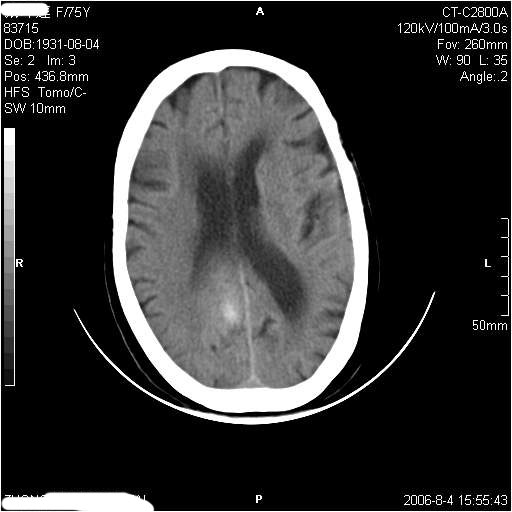

左侧偏瘫3天.

有摔倒外伤史,另看右侧灰白质界限.

应该是右侧大脑镰旁的血肿,右侧基底节区脑梗塞。

2、上纵裂右侧梭形条状高密度影阴,边缘模糊,周围水肿带环绕,右侧脑室受压变形,有摔倒外伤史,多考虑:纵裂硬膜下血肿。

支持纵裂硬膜下血肿,应该是慢性,或是再出血.

右侧大脑镰旁的血肿,右侧基底节区脑梗塞。